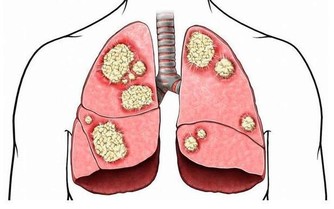

腎小球腎炎、糖尿病腎病、高血壓腎病、痛風腎、多囊腎等都被統稱為“慢性腎病”。當腎臟受損時,患者體內的毒素難以被過濾,逐漸會引起上述症狀。而這類疾病通常無法根治,唯有找到致病原因、確定疾病類型,才能通過相應的治療控制病情,緩解不適感。常見的檢查方法包括血液檢查、放射性核素腎掃描、活體組織檢查等。

如果患者進入了腎病五期,腎功能已經大幅衰竭時,只採取藥物治療和飲食控制遠遠不夠。因為這時的腎臟基本失去了過濾和排除毒素的功能,需要通過腎透析或腎臟移植才能維持正常運轉,但是這兩種方法很有可能會引起嚴重的並發症。